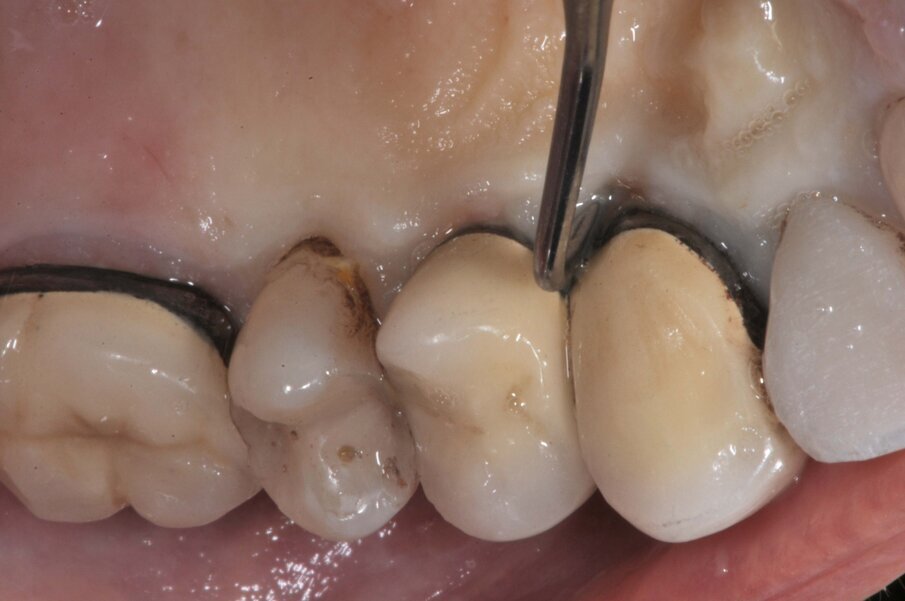

Il dente all’osservazione clinica e radiografica appare devitalizzato e ricostruito per mezzo di una perno moncone fuso e una corona in metallo ceramica collegata ad una corona sul dente 1.4 (Figg. 1, 2). All’esame parodontale si rileva un sondaggio puntiforme in zona palatale che indica la presenza di una frattura radicolare (Fig. 3). La paziente riporta una precedente apicectomia a carico del dente 1.2, come si evince dall’esame come-beam che ne evidenzia gli esiti a carico dell’osso apicale all’elemento 13 (Fig. 4).